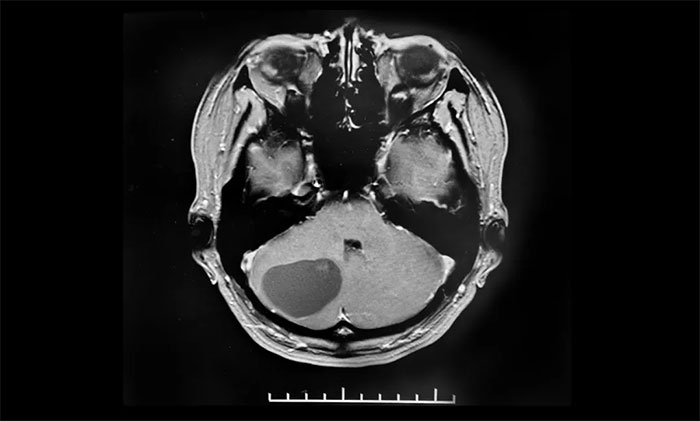

近日,上海蓝十字脑科医院6B神经外二科就收治了一位血管母细胞瘤患者。患者为中年女性,于入院前两个月无明显诱因出现头痛头晕症状,当时未引起重视,未治疗。随着时间推移,入院前一个月,头痛头晕症状加重才就医,最终确诊血管母细胞瘤。后辗转转入上海蓝十字脑科医院,最终经李士其教授手术,顺利切除肿瘤。

▲ 右侧小脑血管母细胞瘤,大小约34x34mm